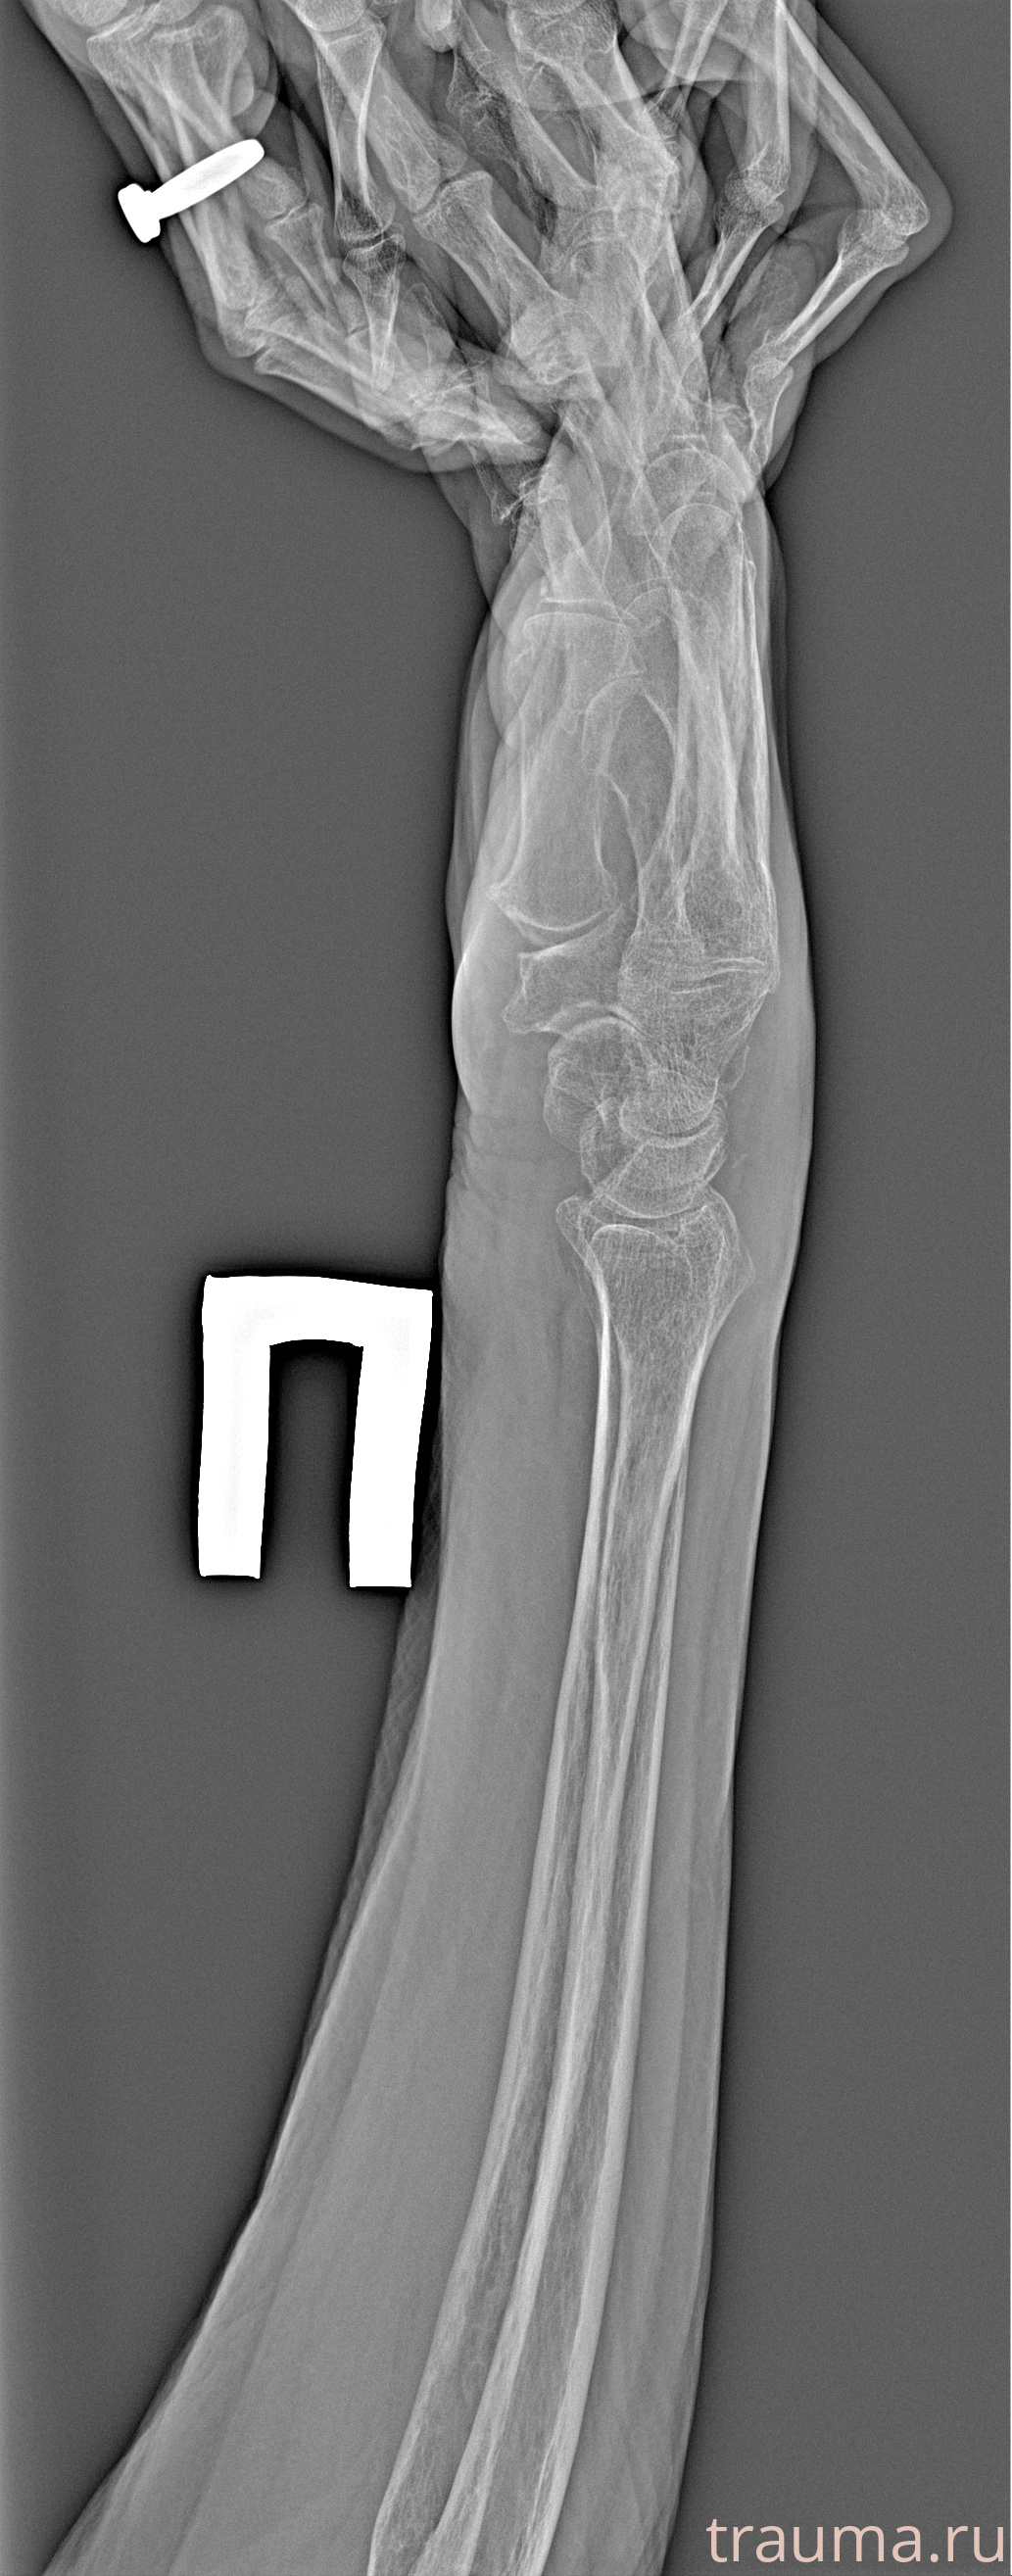

Рентгенограммы

Рентген на дому: по вашему адресу приезжает врач-рентгенолог, травматолог-ортопед с мобильным рентгеновским аппаратом, проводит диагностику травмы или заболевания, делает необходимые рентгенограммы, дает рекомендации по дальнейшему лечению. Получить качественные снимки в домашних условиях возможно благодаря уникальной методике, разработанной МосРентген Центром для института  Склифосовского